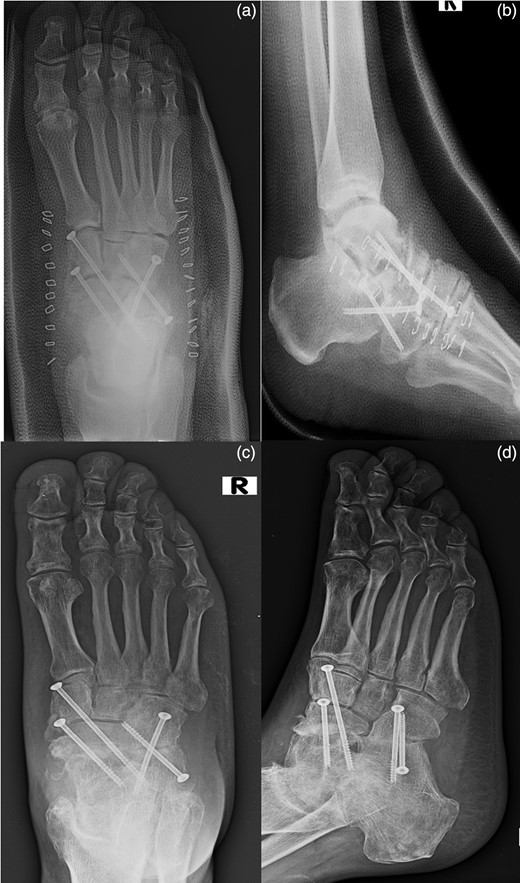

The medial approach was through a longitudinal incision, starting at the tip of the medial malleolus and carried distally 1 cm past the naviculocuneiform joint. The incision was deepened through the capsular tissues. The capsule and spring ligament were stripped from the navicular (Fig. 3).

Lateral approach at the base of the fourth metatarsal, and extended proximally toward the tip of the fibula, ∼1 cm short of the tip to identify the calcaneocuboid joint (a). Medial approach through a longitudinal incision, starting at the tip of the medial malleolus and carried distally 1 cm past the naviculocuneiform joint. It is evident of the antibiotic-loaded cement spacer. (b). An elevator was passed over the dorsal aspect of the talonavicular joint. The antibiotic-loaded cement spacer was removed (c).

An elevator was passed over the dorsal aspect of the talonavicular joint, completely freeing the joint. It was removed the antibiotic-loaded cement spacer.